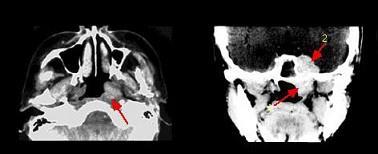

问题 哪项不符合腺样囊性癌的肿瘤(如组图)生物学行为 ( )

选项 A.肿瘤易沿神经生长 B.区域淋巴结转移率高 C.侵袭性极强 D.血行转移率高 E.常出现神经症状

答案 B